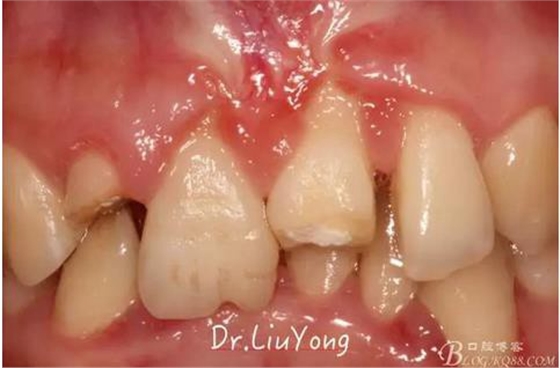

松動牙固定一月后拆除,A1-B2無明顯動度,但牙齦紅腫加重,給予全口齦上下潔治刮治術(shù),上藥,醫(yī)囑加強(qiáng)口腔衛(wèi)生,氯己定漱口液含漱。

術(shù)后兩周復(fù)查,牙齦紅腫明顯好轉(zhuǎn),探診不出血,但是此時A1唇側(cè)牙齦角形退縮1.5mm,B1唇側(cè)牙齦退縮3.5mm,B1遠(yuǎn)中牙齦乳頭萎縮明顯,B2近中牙齦萎縮約1mm,且A1B1B2牙齦退縮處角化牙齦幾乎缺失,同時上唇系帶直接牽拉于B1齦緣?;颊邽楦咝€女性,露齦笑,由于存在前牙區(qū)牙齦的高度嚴(yán)重不對稱及前牙牙冠過長的問題,因此嘗試通過膜齦手術(shù)改善患牙牙齦退縮。通過術(shù)前分析,A1唇側(cè)牙齦退縮屬于Miller分類第一類, B1唇側(cè)牙齦退縮屬于Miller分類第3類(B1遠(yuǎn)中牙齦乳頭為2類,Nordland and Tarnow分類法),B2唇側(cè)牙齦退縮屬于Miller分類第3類,由于擬采用冠向復(fù)位瓣的方式治療牙齦退縮,因此需要先行上唇系帶修整術(shù),解除上唇系帶帶來的過大牽引力。

潔治刮治后2周,如上圖